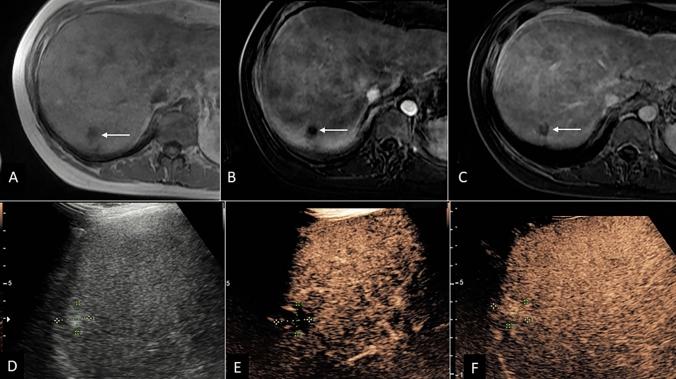

A prospective international multicenter validation study for CEUS Liver Imaging Reporting and Data System (LI-RADS) was conducted between January 2018 and August 2021. 646 patients at risk for HCC with focal liver lesions were enrolled. CEUS was performed using an intravenous ultrasound contrast agent within 4 weeks of CT/MRI. Liver nodules were categorized based on LI-RADS (LR) criteria. Histology or one-year follow-up CT/MRI imaging results were used as the reference standard. The diagnostic performance of CEUS was evaluated for inconclusive CT/MRI scan in two scenarios for which the AASLD recommends repeat imaging or imaging follow-up: observations deemed non-characterizable (LR-NC) or with indeterminate probability of malignancy (LR-3).

75 observations on CT or MRI were categorized as LR-3 (n = 54) or LR-NC (n = 21) CEUS recategorization of such observations into a different LR category (namely, into one among LR-1, LR-2, LR-5, LR-M, or LR-TIV) resulted in management recommendation changes in 33.3% (25/75) and in all but one (96.0%, 24/25) observation, the new management recommendations were correct.

CEUS LI-RADS resulted in management recommendations change in substantial number of liver observations with initial indeterminate CT/MRI characterization, identifying both non-malignant lesions and HCC, potentially accelerating the diagnostic process and alleviating the need for biopsy or follow-up imaging.